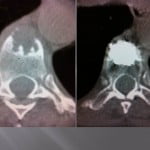

Vertebroplasty techniques in the case of lytic mestastatic lesions or myelomatic with pejorative invasion of the anterior or posterior walls.

The tumoral extension at the posterior wall with or without epidural inflammation constituted a few years ago a counter-indication to vertebroplasty. The experience of conventional radiology teams allowed to progressively reaching that limit. Numerous precautions are necessary to avoid complications.

In case of lytic tumoral lesion invading the posterior wall.

The major risk is compression of the spinal roots by the cement. An excellent radio-opacity of the cement is fundamental to perfectly limit its position and its diffusion under continuous scopic control.

We position the trocar at the level of the most anterior portion of the tumor and cross the adjacent bone. We slowly inject a few drops of cement at the level of the vertebrae not invaded, then as the cement is getting more dense, we withdraw while injecting cement.

The lesion must be filled as much as possible. An bilateral entrance way can be very useful for an optimal filling. In case of a pedicular contact, the withdrawal of the trocar is performed slowly while injecting the rest of the very thick cement little by little to create a bone bridge under scopic guidance. The risk to reach nervous root is important by extension in the foramen, a perfect control of the move s compulsory to avoid nervous complications.